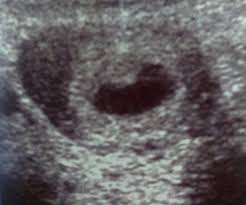

5 ssw ultraschall nur fruchthöhle. In der Frühschwangerschaft können Frauenärzte nicht immer bei der ersten Ultraschalluntersuchung das Baby oder den Herzschlag im Ultraschall erkennen. SSW eine Fruchthöhle und frühestens ab der 6. Guten Abend ich hatte heute meinen 1.

Ultraschallbild Fruchthöhle 5 SSW 3 Beitrag 6 Erstmal herzlichen Glückwunsch zur Schwangerschaft. Allzu viel wirst du auf dem Monitor nicht erkennen können aber bei einer Ultraschalluntersuchung kann ab der 4. Ssw nachdem sich in der 1.

Man konnte nur eine leere fruchthöhle erkennen. Frauenarzt Termin laut Ultraschall bin ich ssw 55 wobei allerdings nur eine leere fruchthöhle zu sehen war von 095cm. Ich habe eine kurze Frage.

SSW 55 Ultraschall keine Fruchthöhle. Ich bin jetzt bei 56 SSW und wir konnten im Ultraschall nur eine leere Fruchthöhle sehen.